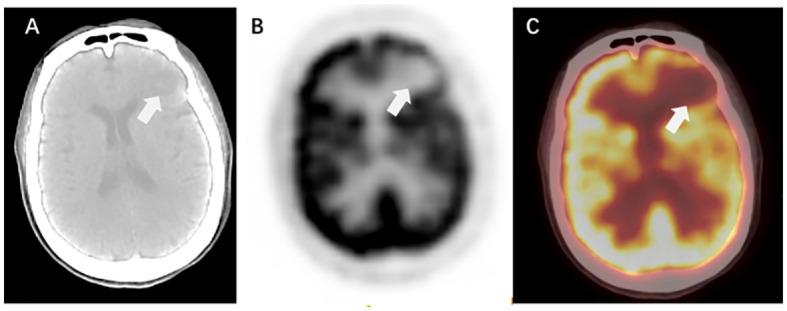

Brain metastases (BMs) are the most prevalent intracranial malignant tumors in adults and are the leading cause of mortality attributed to malignant brain diseases. Radiotherapy (RT) plays a critical role in the treatment of BMs, with local RT techniques such as stereotactic radiosurgery (SRS)/stereotactic body radiotherapy (SBRT) showing remarkable therapeutic effectiveness. The precise determination of gross tumor target volume (GTV) is crucial for ensuring the effectiveness of SRS/SBRT. Multimodal imaging techniques such as CT, MRI, and PET are extensively used for the diagnosis of BMs and GTV determination. With the development of functional imaging and artificial intelligence (AI) technology, there are more innovative ways to determine GTV for BMs, which significantly improve the accuracy and efficiency of the determination. This article provides an overview of the progress in GTV determination for RT in BMs.